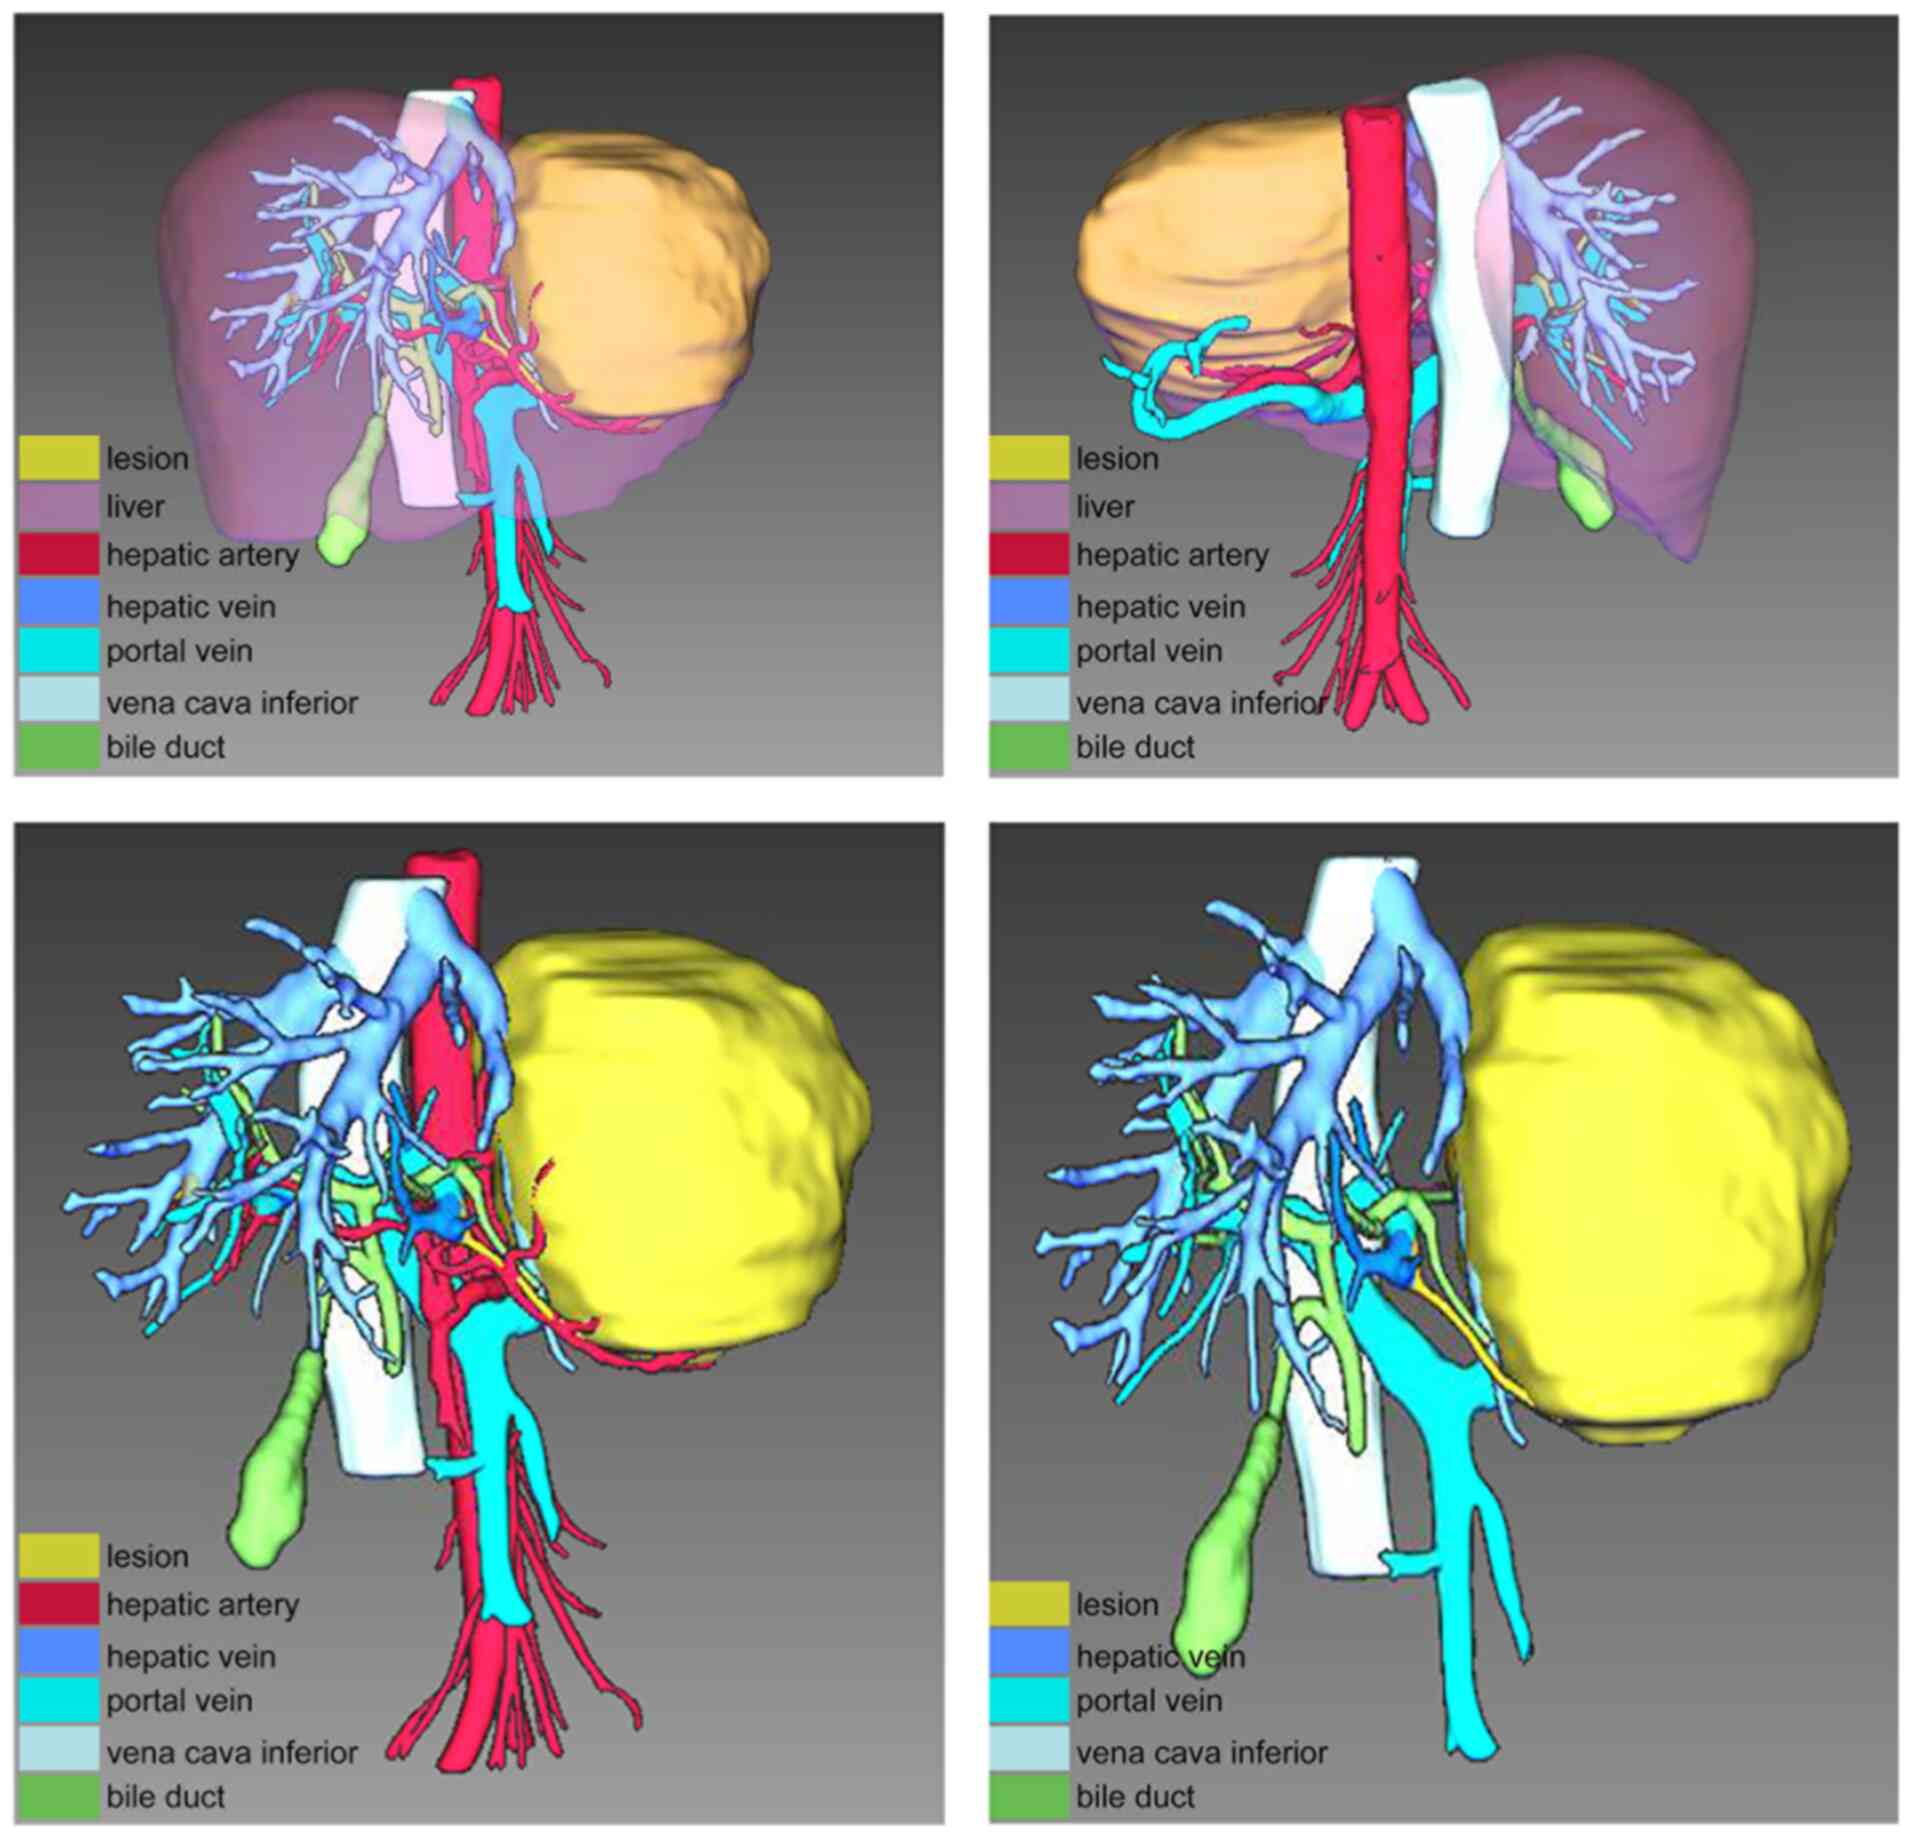

Figure 2.

IQQA-3D (EDDA Technology, Inc.) imaging of the tumor.